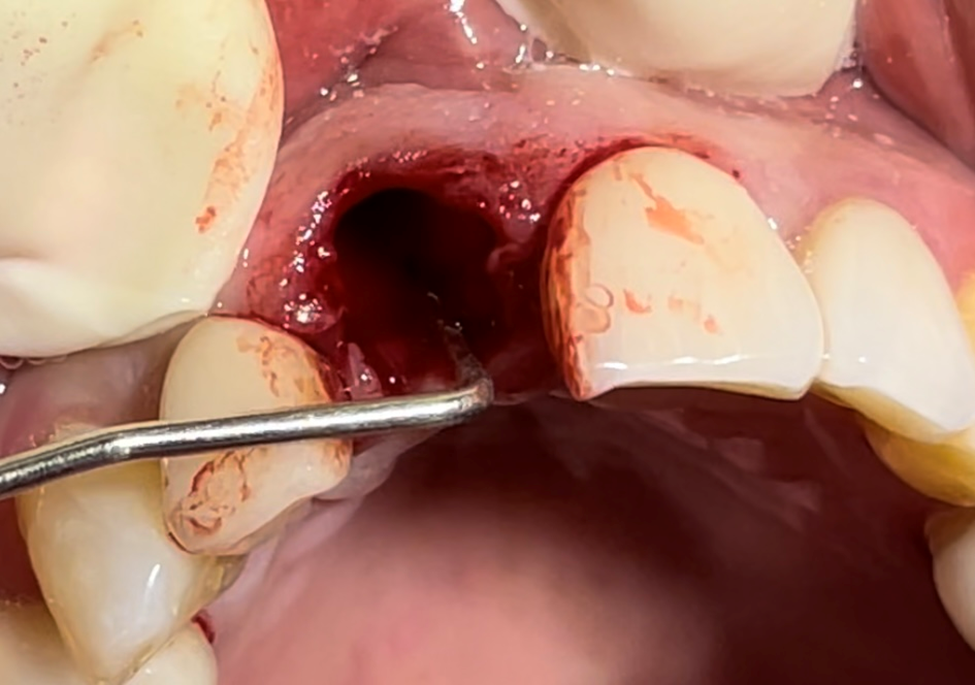

No presente caso, nossa paciente apresentou fratura (Figura 1) da raiz do elemento 11 (incisivo central superior direito), que já era reabilitado com pino intrarradicular (fibra de vidro + núcleo em resina) e coroa protética em cerâmica (dissilicato de lítio). Foi realizada exodontia minimamente traumática (Figuras 2 e 3), com manutenção das paredes ósseas e sem descolamento do tecido gengival ou abertura de retalho. Um implante Maestro (3.5 X 13 mm) foi instalado em posição tridimensional adequada e guiada pelo planejamento protético, no qual optamos por uma coroa parafusada (Figura 4). A profundidade de instalação foi conforme preconizada para um implante CM, e em seguida, um medidor de profundidade foi utilizado para selecionar o transmucoso do componente protético. Foi selecionado um pilar Ideale (3.3 X 4 mm) com transmucoso de 2.5 mm, favorecendo a adaptação dos tecidos moles e estabelecimento das distâncias biológicas peri-implantares (Figura 5).